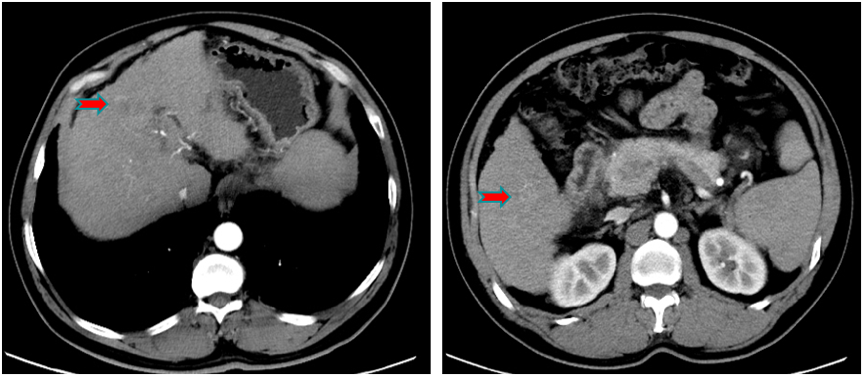

术前CT示,肝内可见多发肿块,符合肝细胞癌CT表现;术前MRI示,DWI信号明显增浓(图1)。

图1.2020年6月入院前CT和MRI